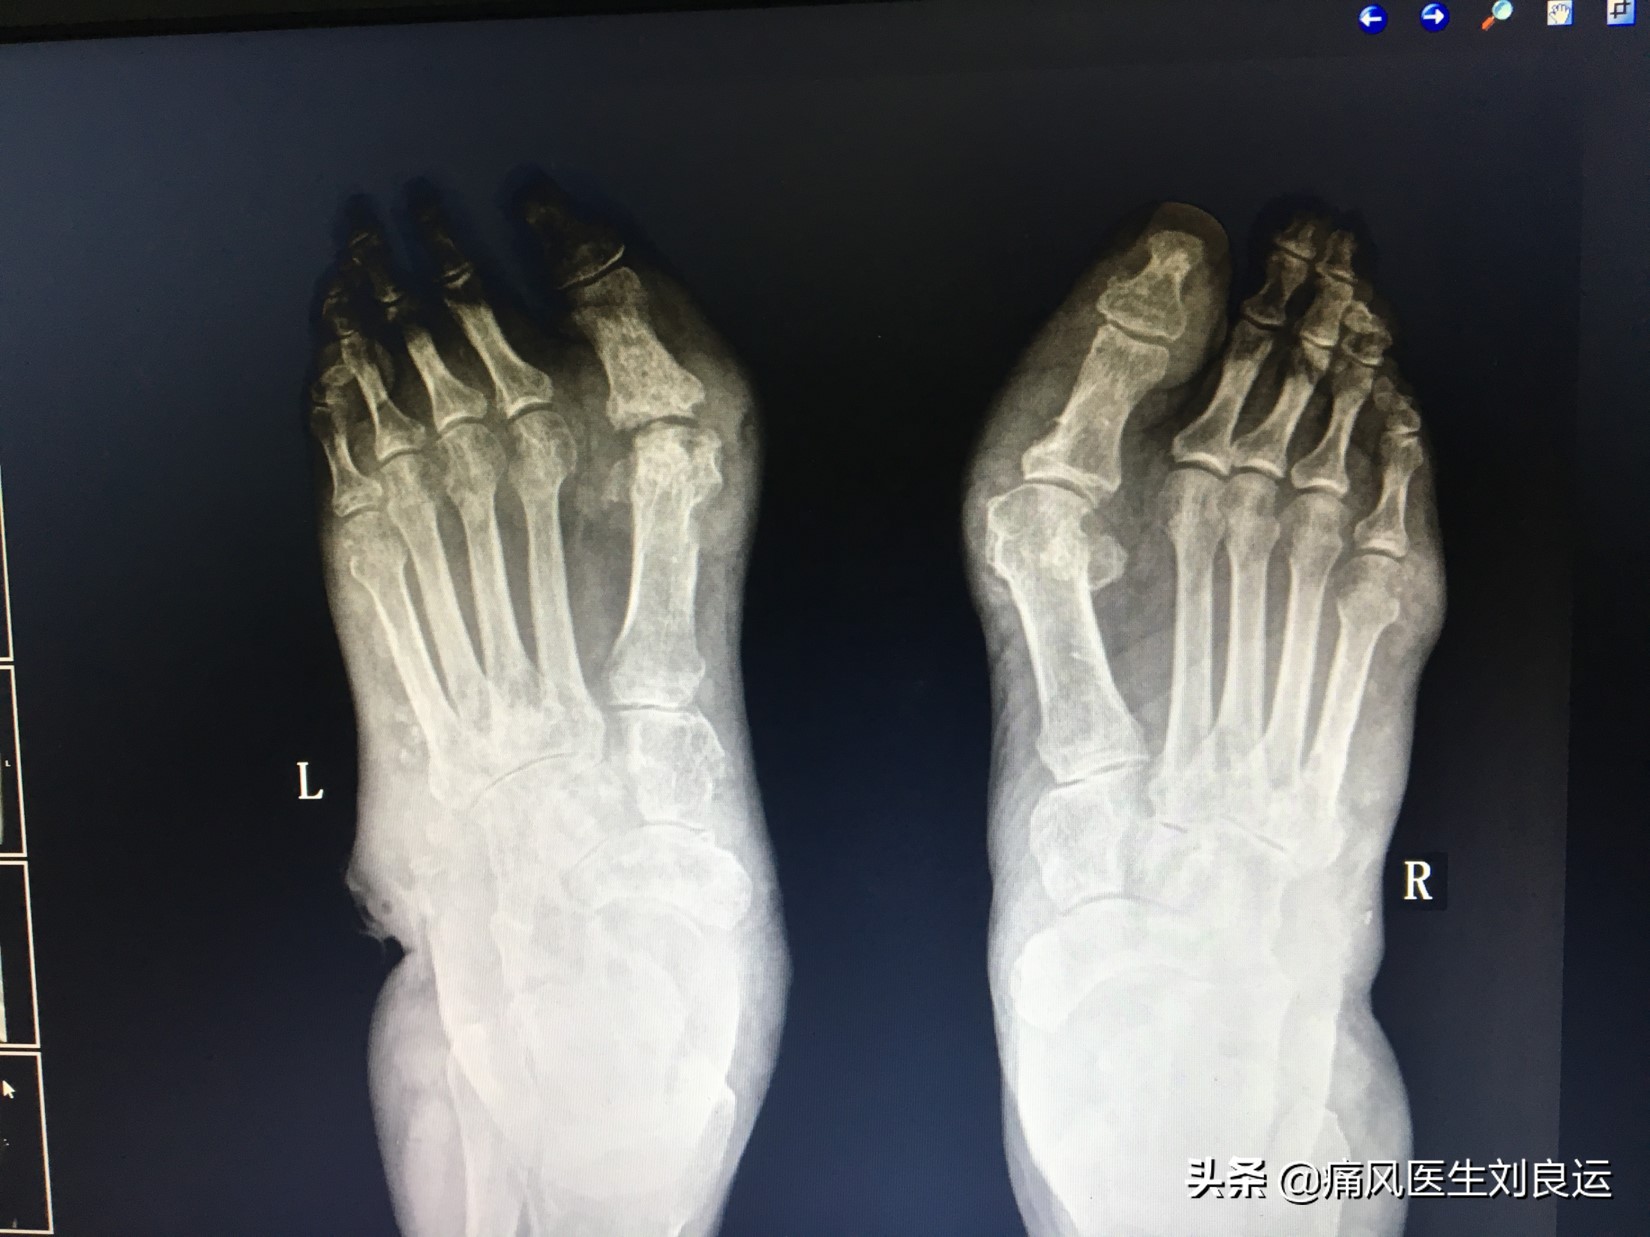

X线下双足痛风石

随着痛风病情进展,往往会引起大小不一的痛风石的发生。痛风石的出现,意味着痛风病程已经进入了第四阶段,疾病已经越发严重了,如果继续放任痛风发展,痛风就要开始“攻占”*体器人官**了。痛风石可分布于全身各部位,早期无明显症状,随着疾病的发展可出现局部破溃甚至坏死,少有继发感染,位于骨骼关节的痛风石可引起骨骼关节的破坏,严重时可导致畸形、截肢。

痛风石是痛风的特征性改变,痛风石的形成与病程、血尿酸水平有关。病程越长,发生痛风石的几率就越大。高尿酸血症持续时间越长,越易发生痛风石。反之,痛风石越多、越大,表明高尿酸血症未得到很好控制,即病情越重。有些患者,病程虽己很长,但治疗后血尿酸长期保持在正常范围内,很少发生痛风石。痛风石不同病情有不同的临床表现: